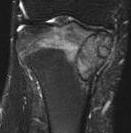

MRI

Rarely diagnostic

- high signal intensity on T2